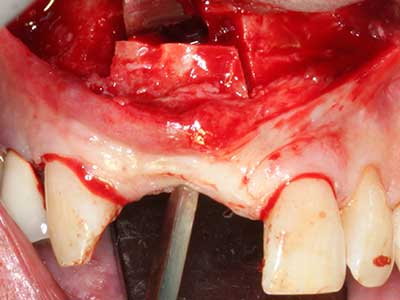

Indikation: Bone Splitting

Knochengewebe ist nicht nur rein mineralisch, sondern auch in wesentlichen Anteilen aus Kollagenfasern aufgebaut. Dies gewährleistet neben einer guten Druckfestigkeit eine gewisse Flexibilität, welche für die Durchführung von Augmentationen genutzt werden kann. Bei der klassischen Expansionsplastik im Sinne eines Bone Splittings wird der atrophierte Kieferkamm in seiner Längsachse gespalten und nach Erreichen einer ausreichenden Osteotomietiefe vorsichtig aufgedehnt (Abb. 13-16), idealerweise ohne den Kiefer wesentlich zu deperiostieren (Brugnami, Caiazzo et al. 2014, Stricker, Fleiner et al. 2014). Bewährt haben sich Schrauben- und Plattensysteme mit zunehmender Expansionsdistanz, um die beiden Knochenlamellen unterhalb der Bruchschwelle voneinander zu distanzieren. In der Regel werden Restknochenbreiten von mindestens 3-4 mm gefordert (Chiapasco, Zaniboni et al. 2006), um eine ausreichende Flexibilität und knöcherne Bedeckung der einzubringenden Implantate zu gewährleisten. Ggf. kann eine ein- oder beidseitige vertikale Entlastungsosteotomie die Flexibilität verbessern. Als Alternative zur klassischen Technik wurde eine Kombination mit weiteren augmentativen Techniken vor allem auf der bukkalen Seite beschrieben.

Mittels Piezosägen erfolgt die Anlage des Splittings besonders schonend und ohne wesentliche Dimensionsverluste, so dass sich keine signifikanten Unterschiede von Implantaten im gesplitteten Kiefer im Vergleich zum nicht defizitären Alveolarkamm gezeigt haben (Chiapasco, Zaniboni et al. 2006, Danza, Guidi et al. 2009). Gerade beim lokal begrenzten und tiefen Splitting ist jedoch stets auf eine ausreichende Wasserkühlung zu achten, um thermische Belastungen in den apikalen Osteotomiebereichen zu vermeiden.